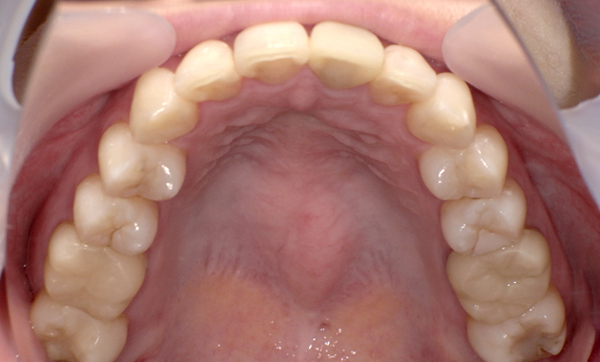

症例_010 「出っ歯」症例

治療期間:7ヶ月金額:30万円+税20代女性出っ歯捻転歯上の前歯だけ

| Before | After |